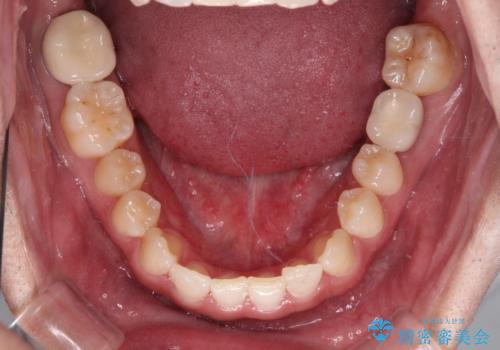

- 上顎前歯の隙間を気にして来院された患者様です。

下顎前歯に叢生がありましたが、特に気にしていらっしゃいませんでした。

下顎臼歯にインプラント補綴治療がされており、全顎治療するにはクラウンの作り替えが必要となる旨を説明し、ワイヤー装置により上顎のみの矯正治療を行うこととしました。

下顎前歯の叢生解消も提案しましたが、上顎の隙間が閉じたことで満足されました。

空隙歯列弓はマウスピースによる保定を行っても、すぐに後戻りを起こしてしまうため、ワイヤーリテーナーによる保定を併用することとしました。